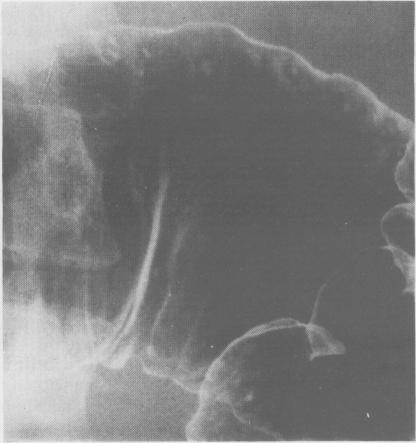

The case is described of a young Asian woman with massive rectal haemorrhage during and after pregnancy. Barium radiology showed aphthoid ulcers in the colon and changes in the ileum suggesting tuberculosis. Colonoscopy revealed hyperplastic ulceration in the terminal ileum and culture of biopsies from this area grew Mycobacterium tuberculosis. The patient made a full and rapid recovery on anti-tuberculous therapy. Colonic aphthoid ulceration has not previously been recorded, radiologically, in intestinal tuberculosis.